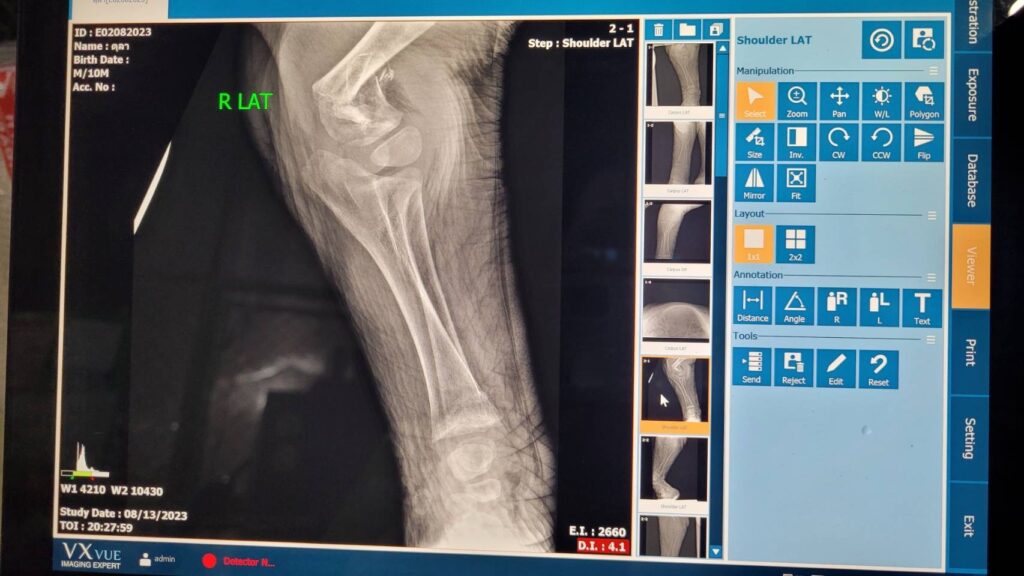

สัตวแพทย์ลงความเห็นเบื้องต้นถึงสาเหตุการล้มว่า เกิดการภาวะบาดเจ็บรุนแรงของกระดูกต้นขาหน้าทั้ง 2 ขา หัก (Humerus fracture) ทำให้เกิดการช็อกตามมา (Pain shock)

ด้านนายเผด็จ ลายทอง ผู้อำนวยสำนักอนุรักษ์สัตว์ป่า ร่วมกับทีมสัตวแพทย์ทำการชันสูตรเพื่อหาสาเหตุและเก็บตัวอย่างส่งตรวจทางปฏิบัติการเพื่อยืนยันถึงสาเหตุการเสียชีวิต ปรากฏว่า สาเหตุหลักในการเสียชีวิต เกิดจากสภาวะกระดูกบางทั่วร่างกาย โดยเฉพาะบริเวณขาหน้า (ด้านบน) ทั้งสองข้าง พบการสลายของกระดูก ทำให้กระดูกแตกหักละเอียด ผิดรูป ซึ่งเป็นสาเหตุของอาการไม่ล้มตัวลงนอน และเล่นกับพี่เลี้ยงตามปกติ อวัยวะภายในร่างกายพบว่า ลำไส้มีความแดงผิดปกติ และสัตวแพทย์ได้ทำการเก็บตัวอย่างอวัยวะทั้งหมด รวมถึงกระดูก ส่งทางห้องปฏิบัติการ คณะสัตวแพทยศาสตร์ มหาวิทยาลัยเกษตรศาสตร์ วิทยาเขตกำแพงแสน คณะสัตวแพทยศาสตร์ จุฬาลงกรณ์มหาวิทยาลัย คณะสัตวแพทยศาสตร์ มหาวิทยาลัยมหิดล และ ศูนย์พัฒนาการทางสัตวแพทย์ภาคตะวันออก กรมปศุสัตว์